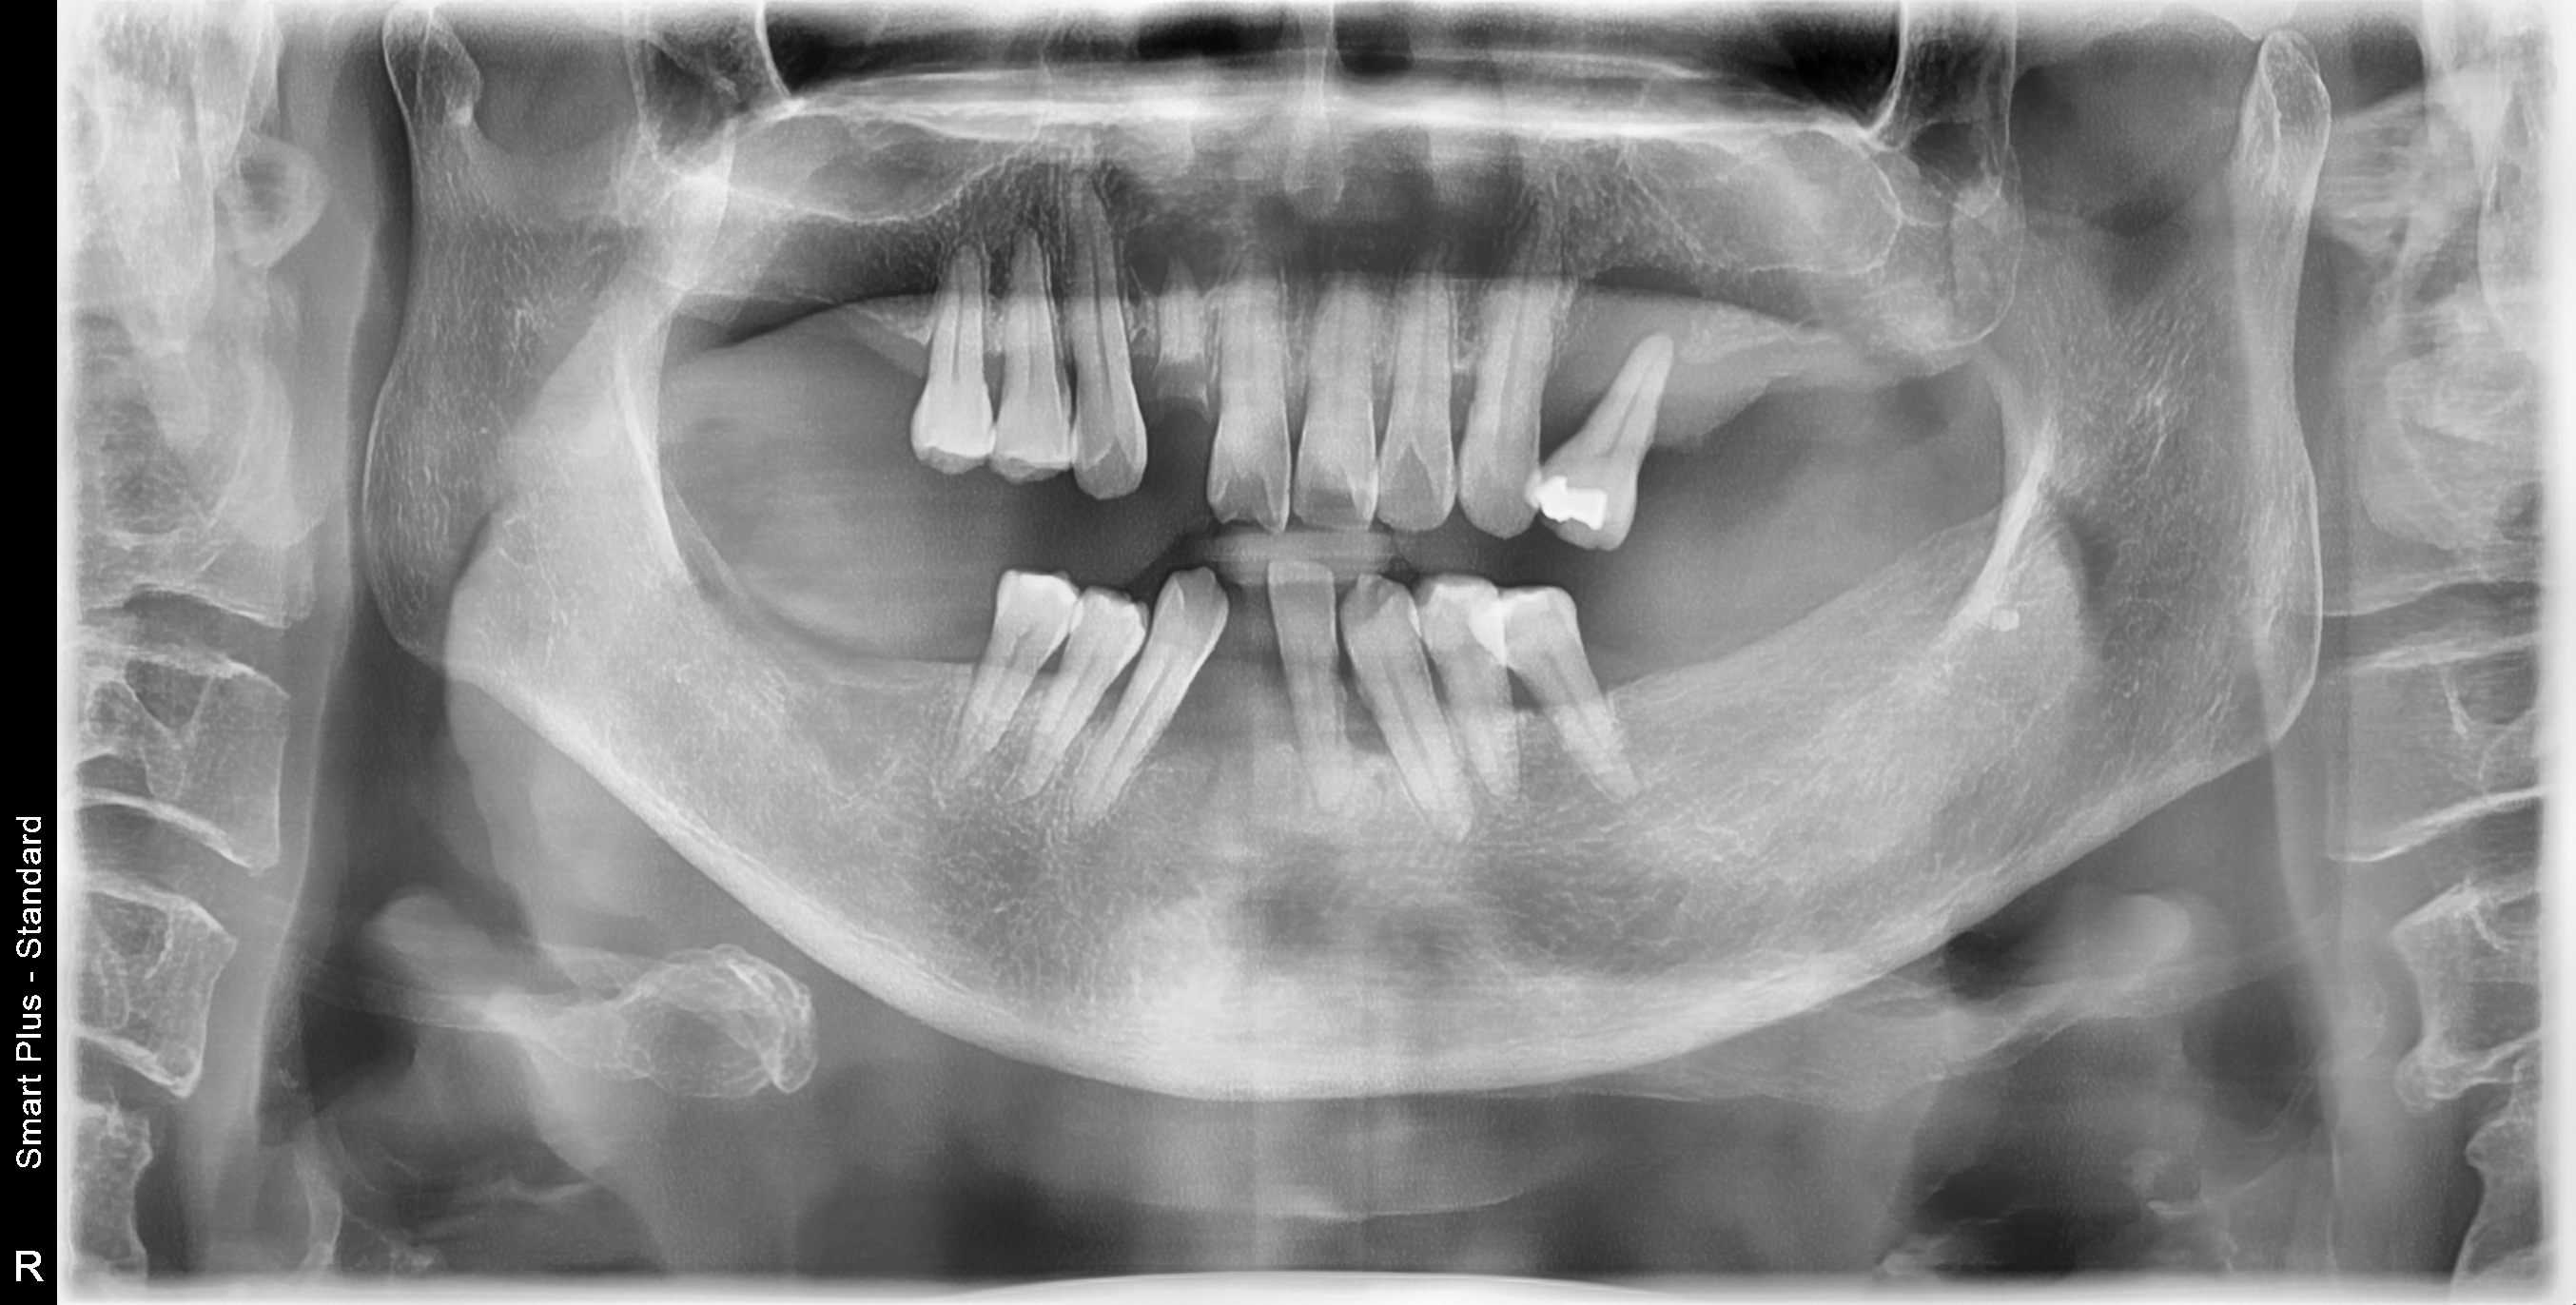

[임플란트] 제목 : 치주환자의 보철치료

60대 치주환자의 보철치료